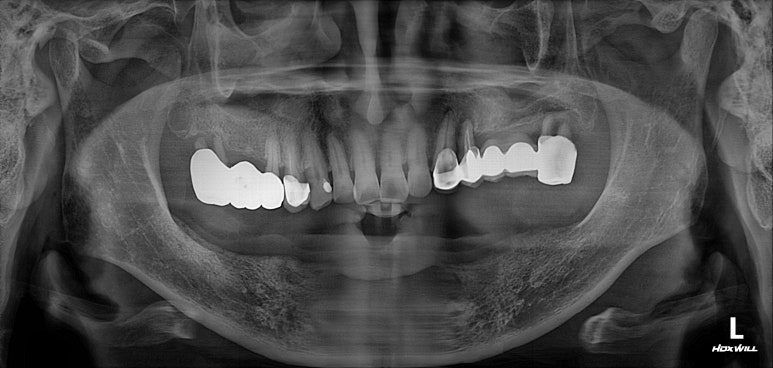

처음 내원하셨을 때 치과용 파노라마 소견입니다.

아래는 이가 하나도 없어 얼마 전 다른 치과에서 제작한 전체틀니를 사용하고 계셨고,

위 어금니는 브릿지로 되어있는데 만성치주염으로 흔들거리는 상황이었습니다.